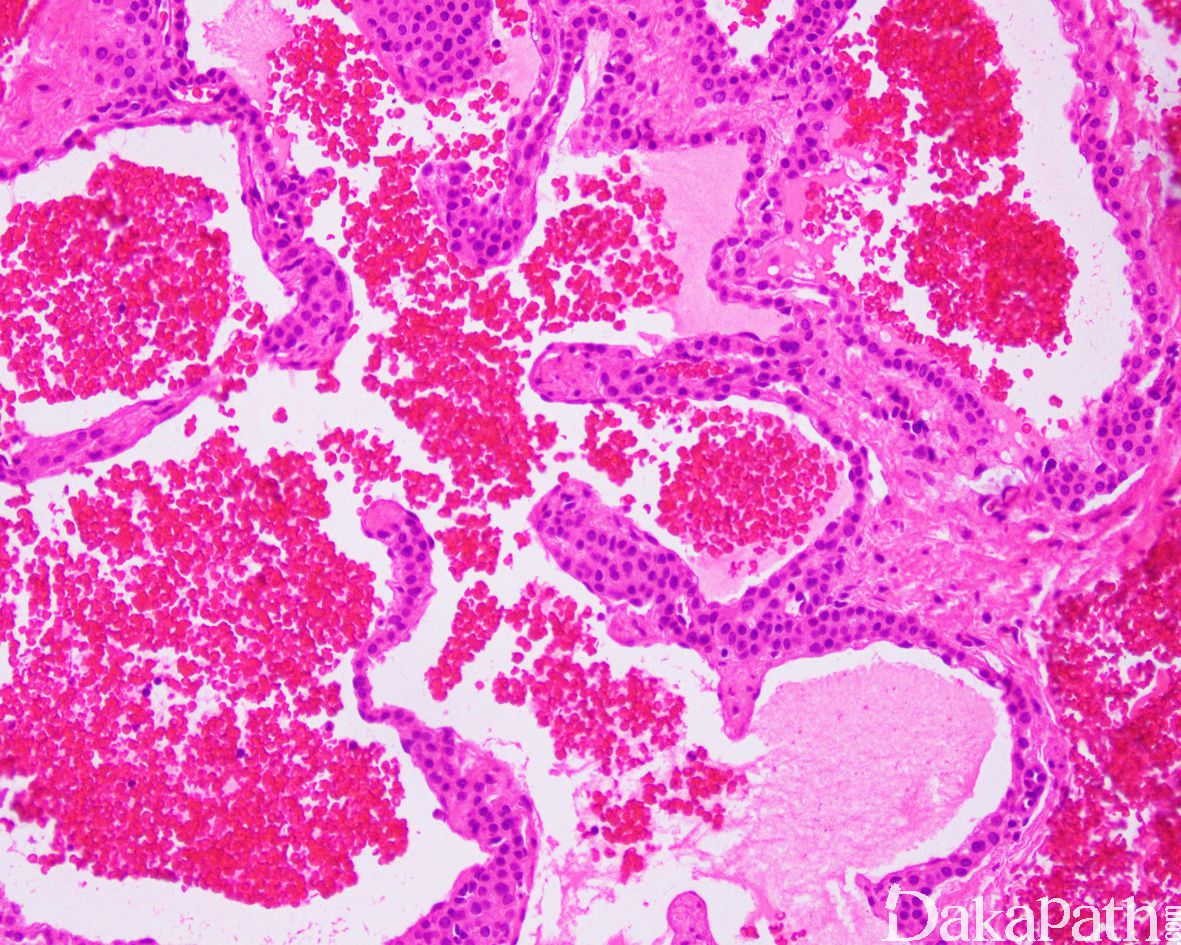

- 总体结构上表现为呈浸润性生长的口径大小不等的血管瘤/弥漫性血管瘤,血管壁内可见血管球瘤样结节生长;